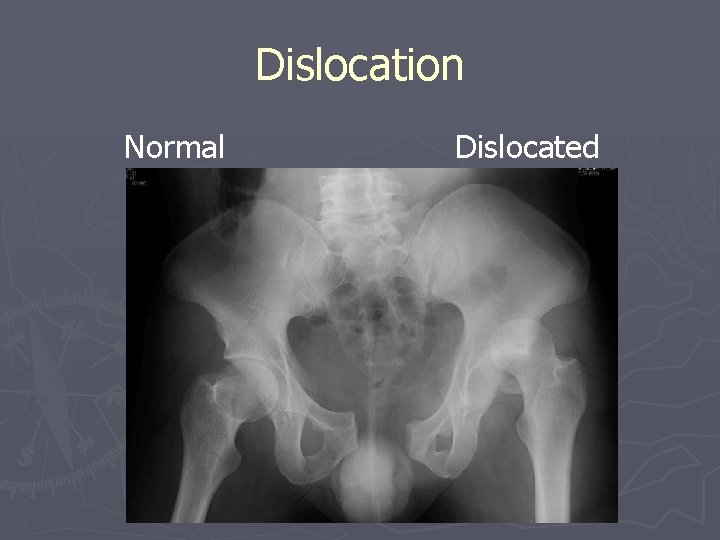

Problems with Skeletal System Dislocation Normal Dislocated

Dislocation Normal Dislocated